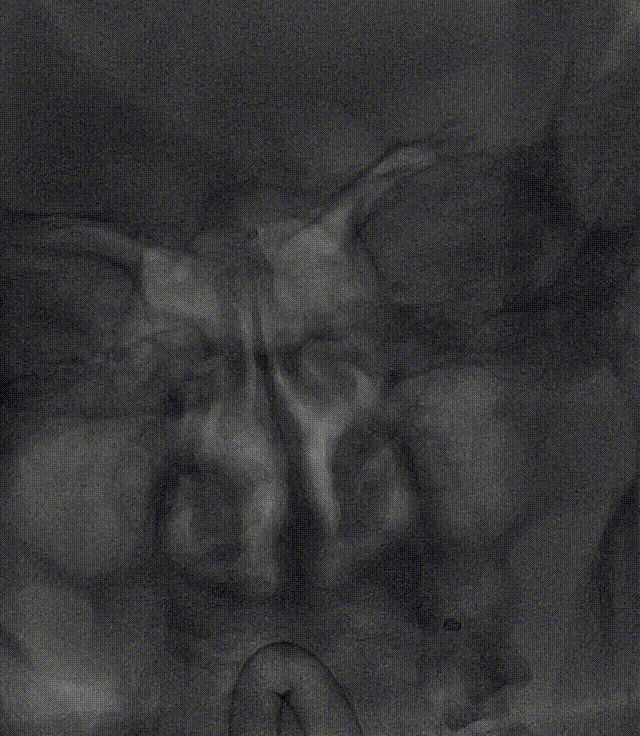

运用BASIS技术植入3.0*25mm Syphonet®取栓支架,输送球囊对闭塞段进行扩张。

运用BASIS技术回收3.0*25mm Syphonet®取栓支架及6F 125cm Tethys®中间导引导管,取出血栓,并在左侧椎动脉V4段残余狭窄处置入颅内支架系统;

复查造影:左侧椎动脉、双侧大脑后动脉、小脑上动脉、小脑前下动脉显影正常。

术中取出的血栓。

运用BASIS技术回收3.0*25mm Syphonet®取栓支架及5F 125cm Tethys®中间导引导管,取出血栓;